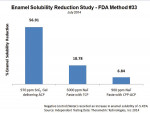

The Enamelon products were then tested to assess resistance of enamel to acid challenges (using method #33 in the US FDA Anticaries Drug Products for OTC Human Use, Final Monograph testing procedures). The Enamelon Preventive Treatment Gel (970 ppm F- ion) provided 3 times greater reduction in enamel solubility than the 5,000-ppm fluoride ion prescription-strength toothpaste and 8 times greater reduction than the 900-ppm fluoride ion product containing CCP-ACP (Figure 7) (independent testing data: Therametric Technologies, Inc., 2014).

It is important to explain the nature and use of these concentrated stannous fluoride products to parents and especially to children old enough to understand the purpose of these protocols. To date, patients have reported that the Enamelon products have a pleasant taste, and parents have been compliant with having their children use the new gel and toothpaste. In view of the lower amount of fluoride content in the treatment gel, the increased fluoride uptake shown in Figure 6, and the increased resistance to acid challenge of treated enamel as shown in Figure 7, the authors expect Enamelon Gel to be a valuable preventive dentistry adjunct in the overall care of high-caries-risk children and teenagers, especially those wearing fixed orthodontic appliances.